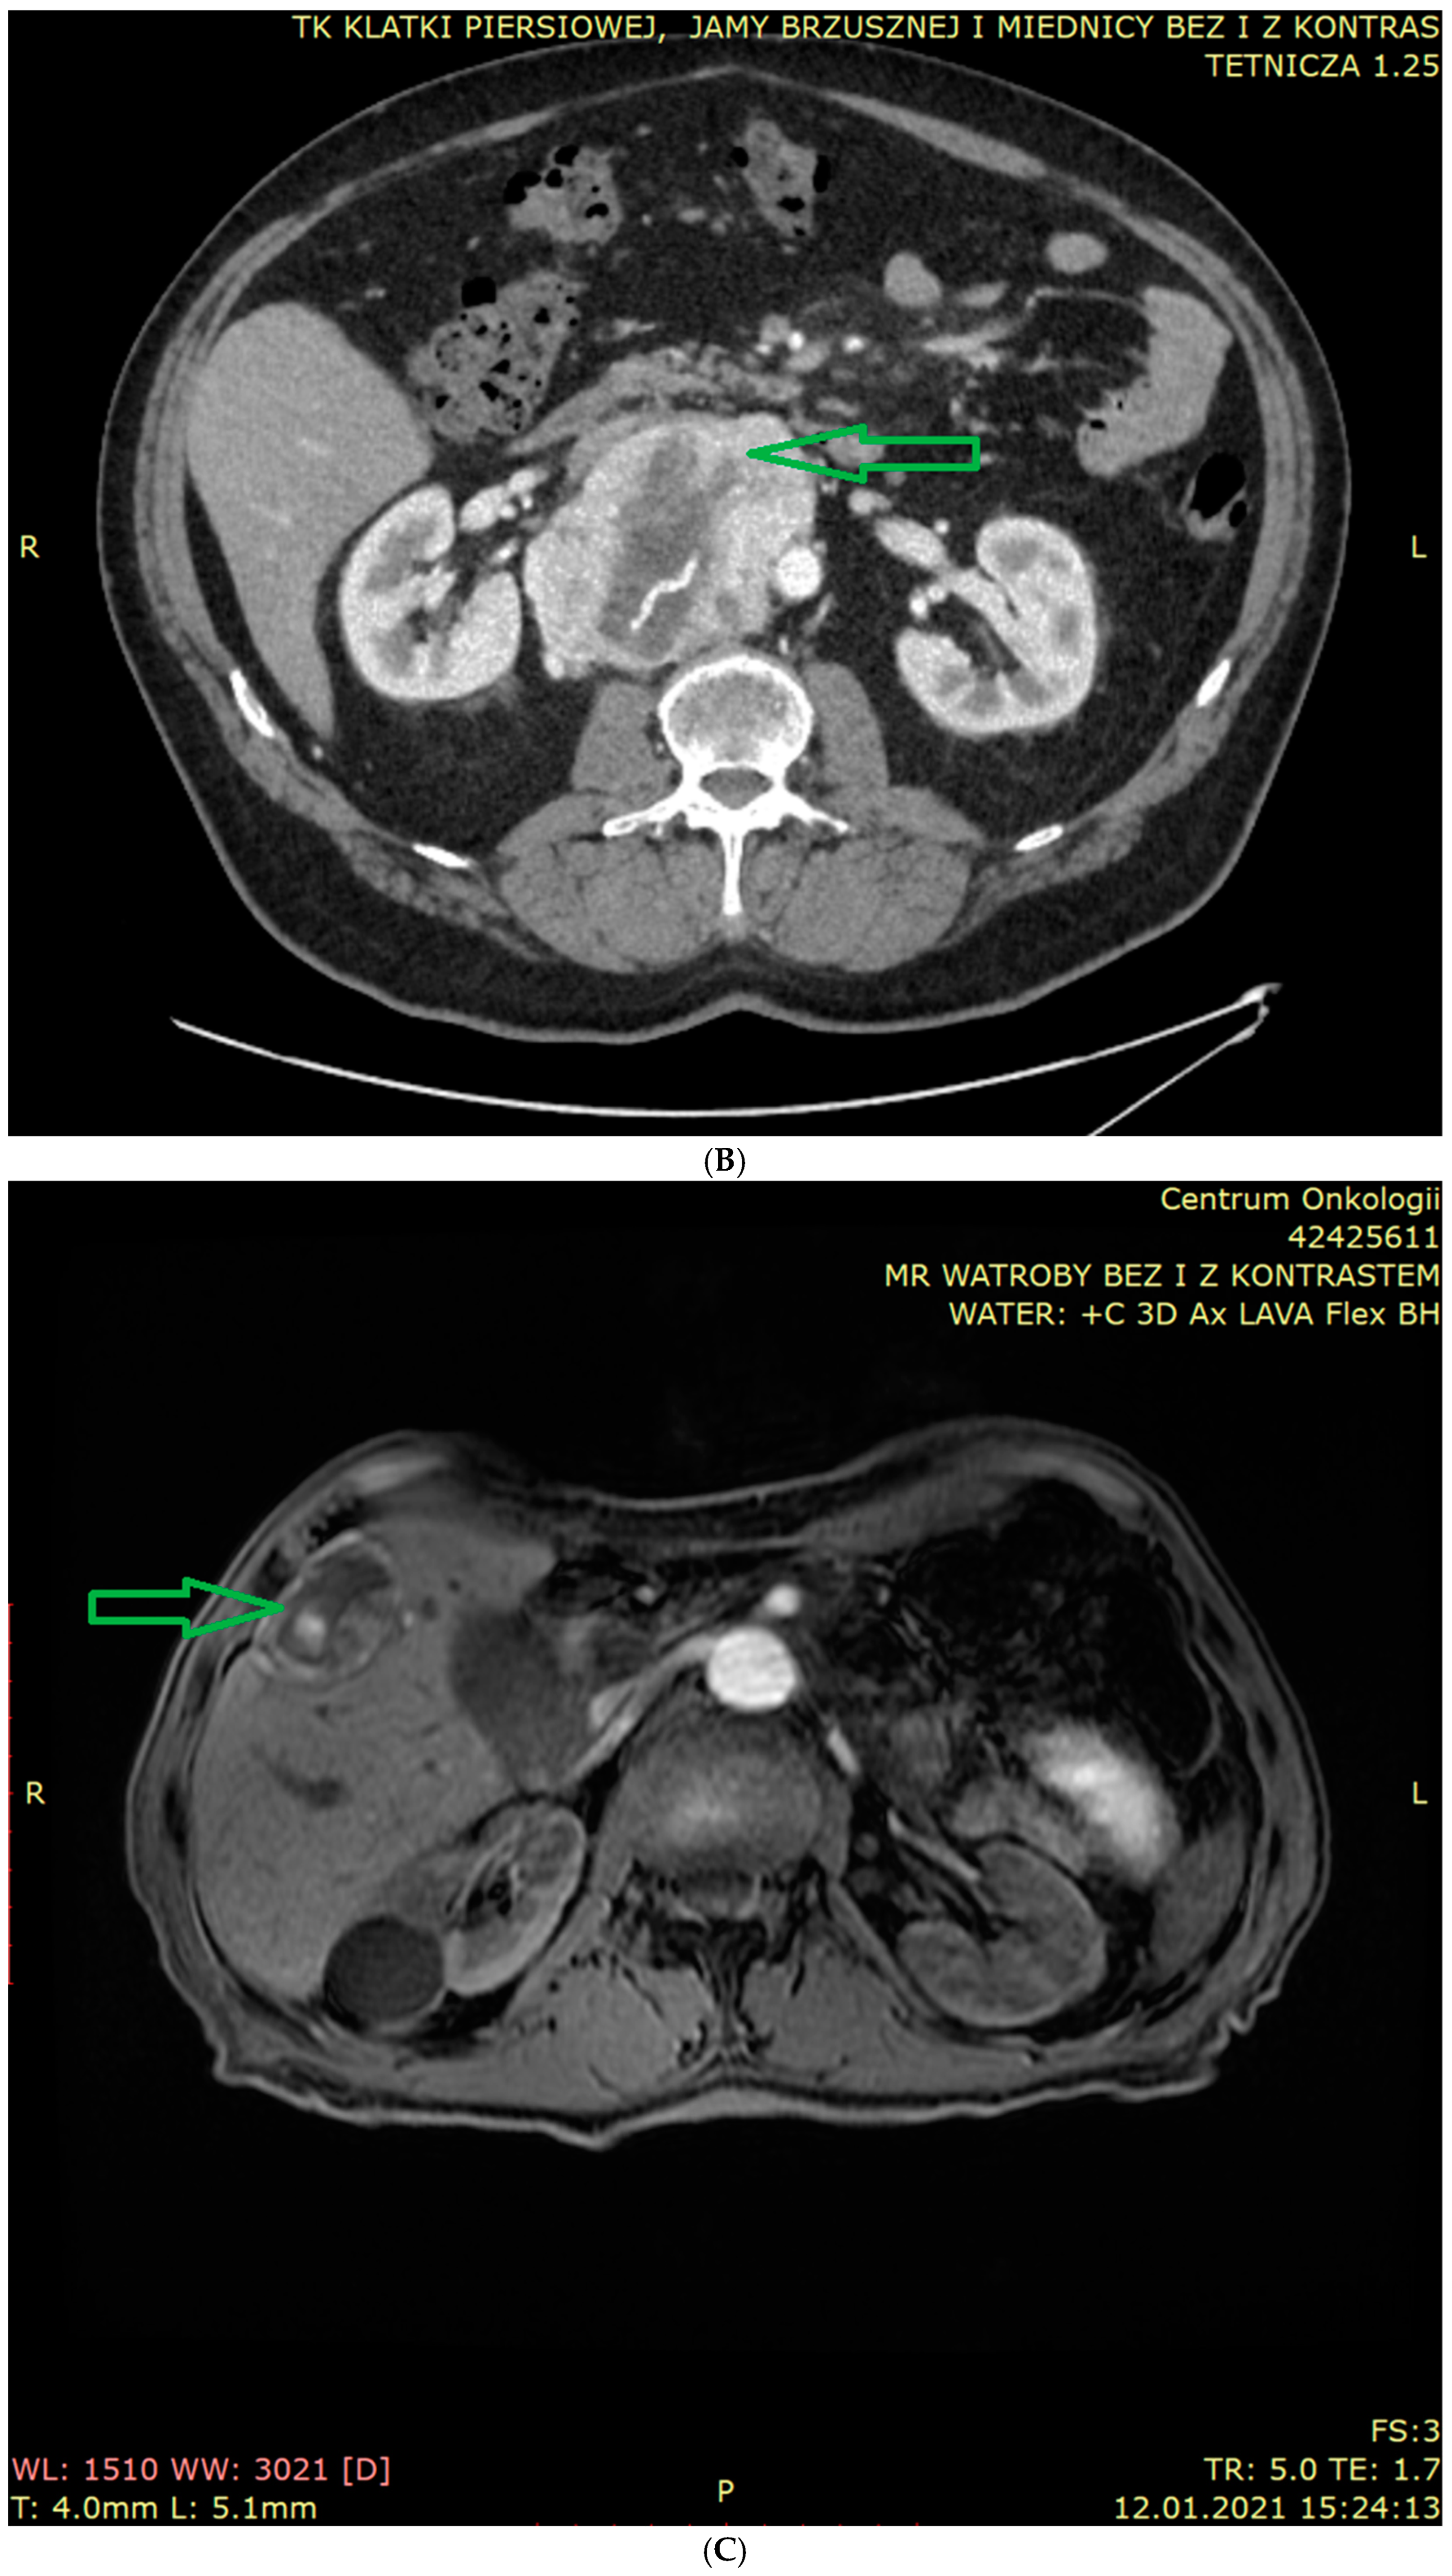

6.1. Anatomical Imaging

6.2. Functional Imaging